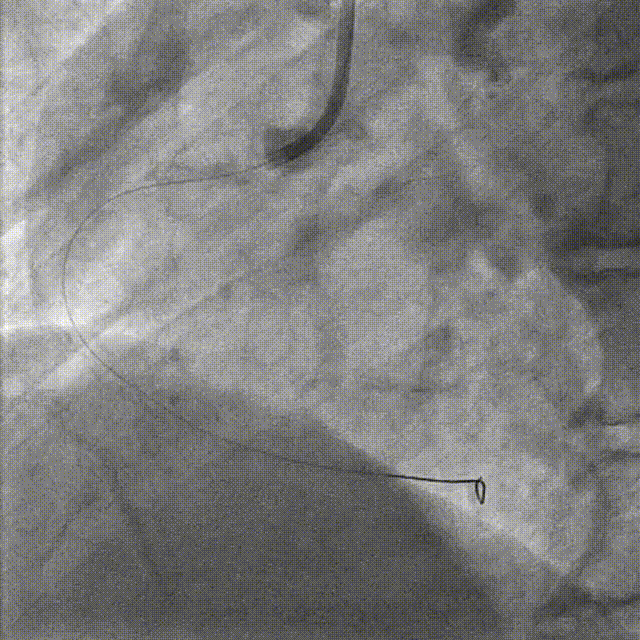

Final Results